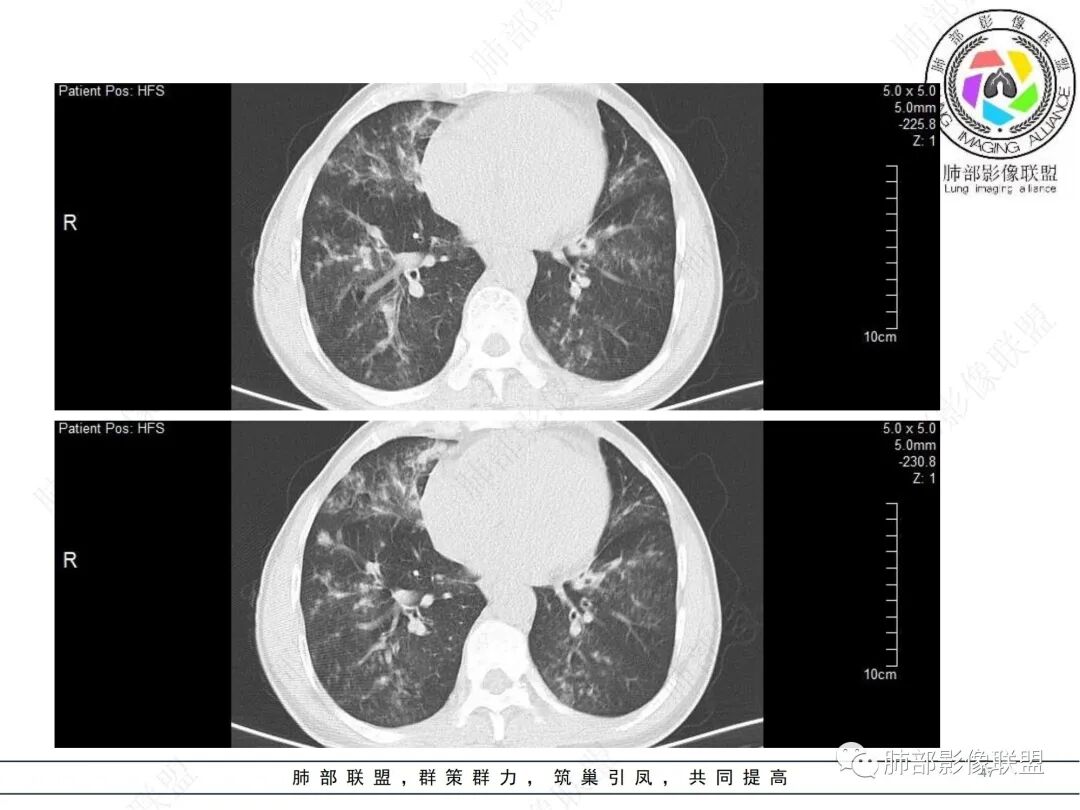

58岁男性,咳嗽胸闷3天,咳较多褐粘液痰,无发热。有2型糖尿病病史。白细胞与中性粒细胞升高。CRP升高。鳞状上皮细胞癌抗原轻度升高。结核T细胞免疫斑点实性阳性。肺炎支原体、衣原体IgG轻度升高。支气管镜显示支气管炎性改变、右肺下叶背段管腔狭窄。2.影像特点:

2022.6.24CT显示两肺弥漫性段、亚段支气管壁增厚(两肺各叶都累及),增厚的支气管壁外可见沿着支气管分布的渗出、实变影。另外远端肺内亦可见多发树芽影、结节影,其边界欠清晰。右肺下叶基底段局部胸膜下亦可见小斑片影,边界不清。2022.6.27CT显示两肺增厚的支气管壁外的渗出实变影明显增多、范围更广。远端肺内病灶亦增多、范围增大。部分位于胸膜下的病灶可见侧向融合趋势。3.病例分析: